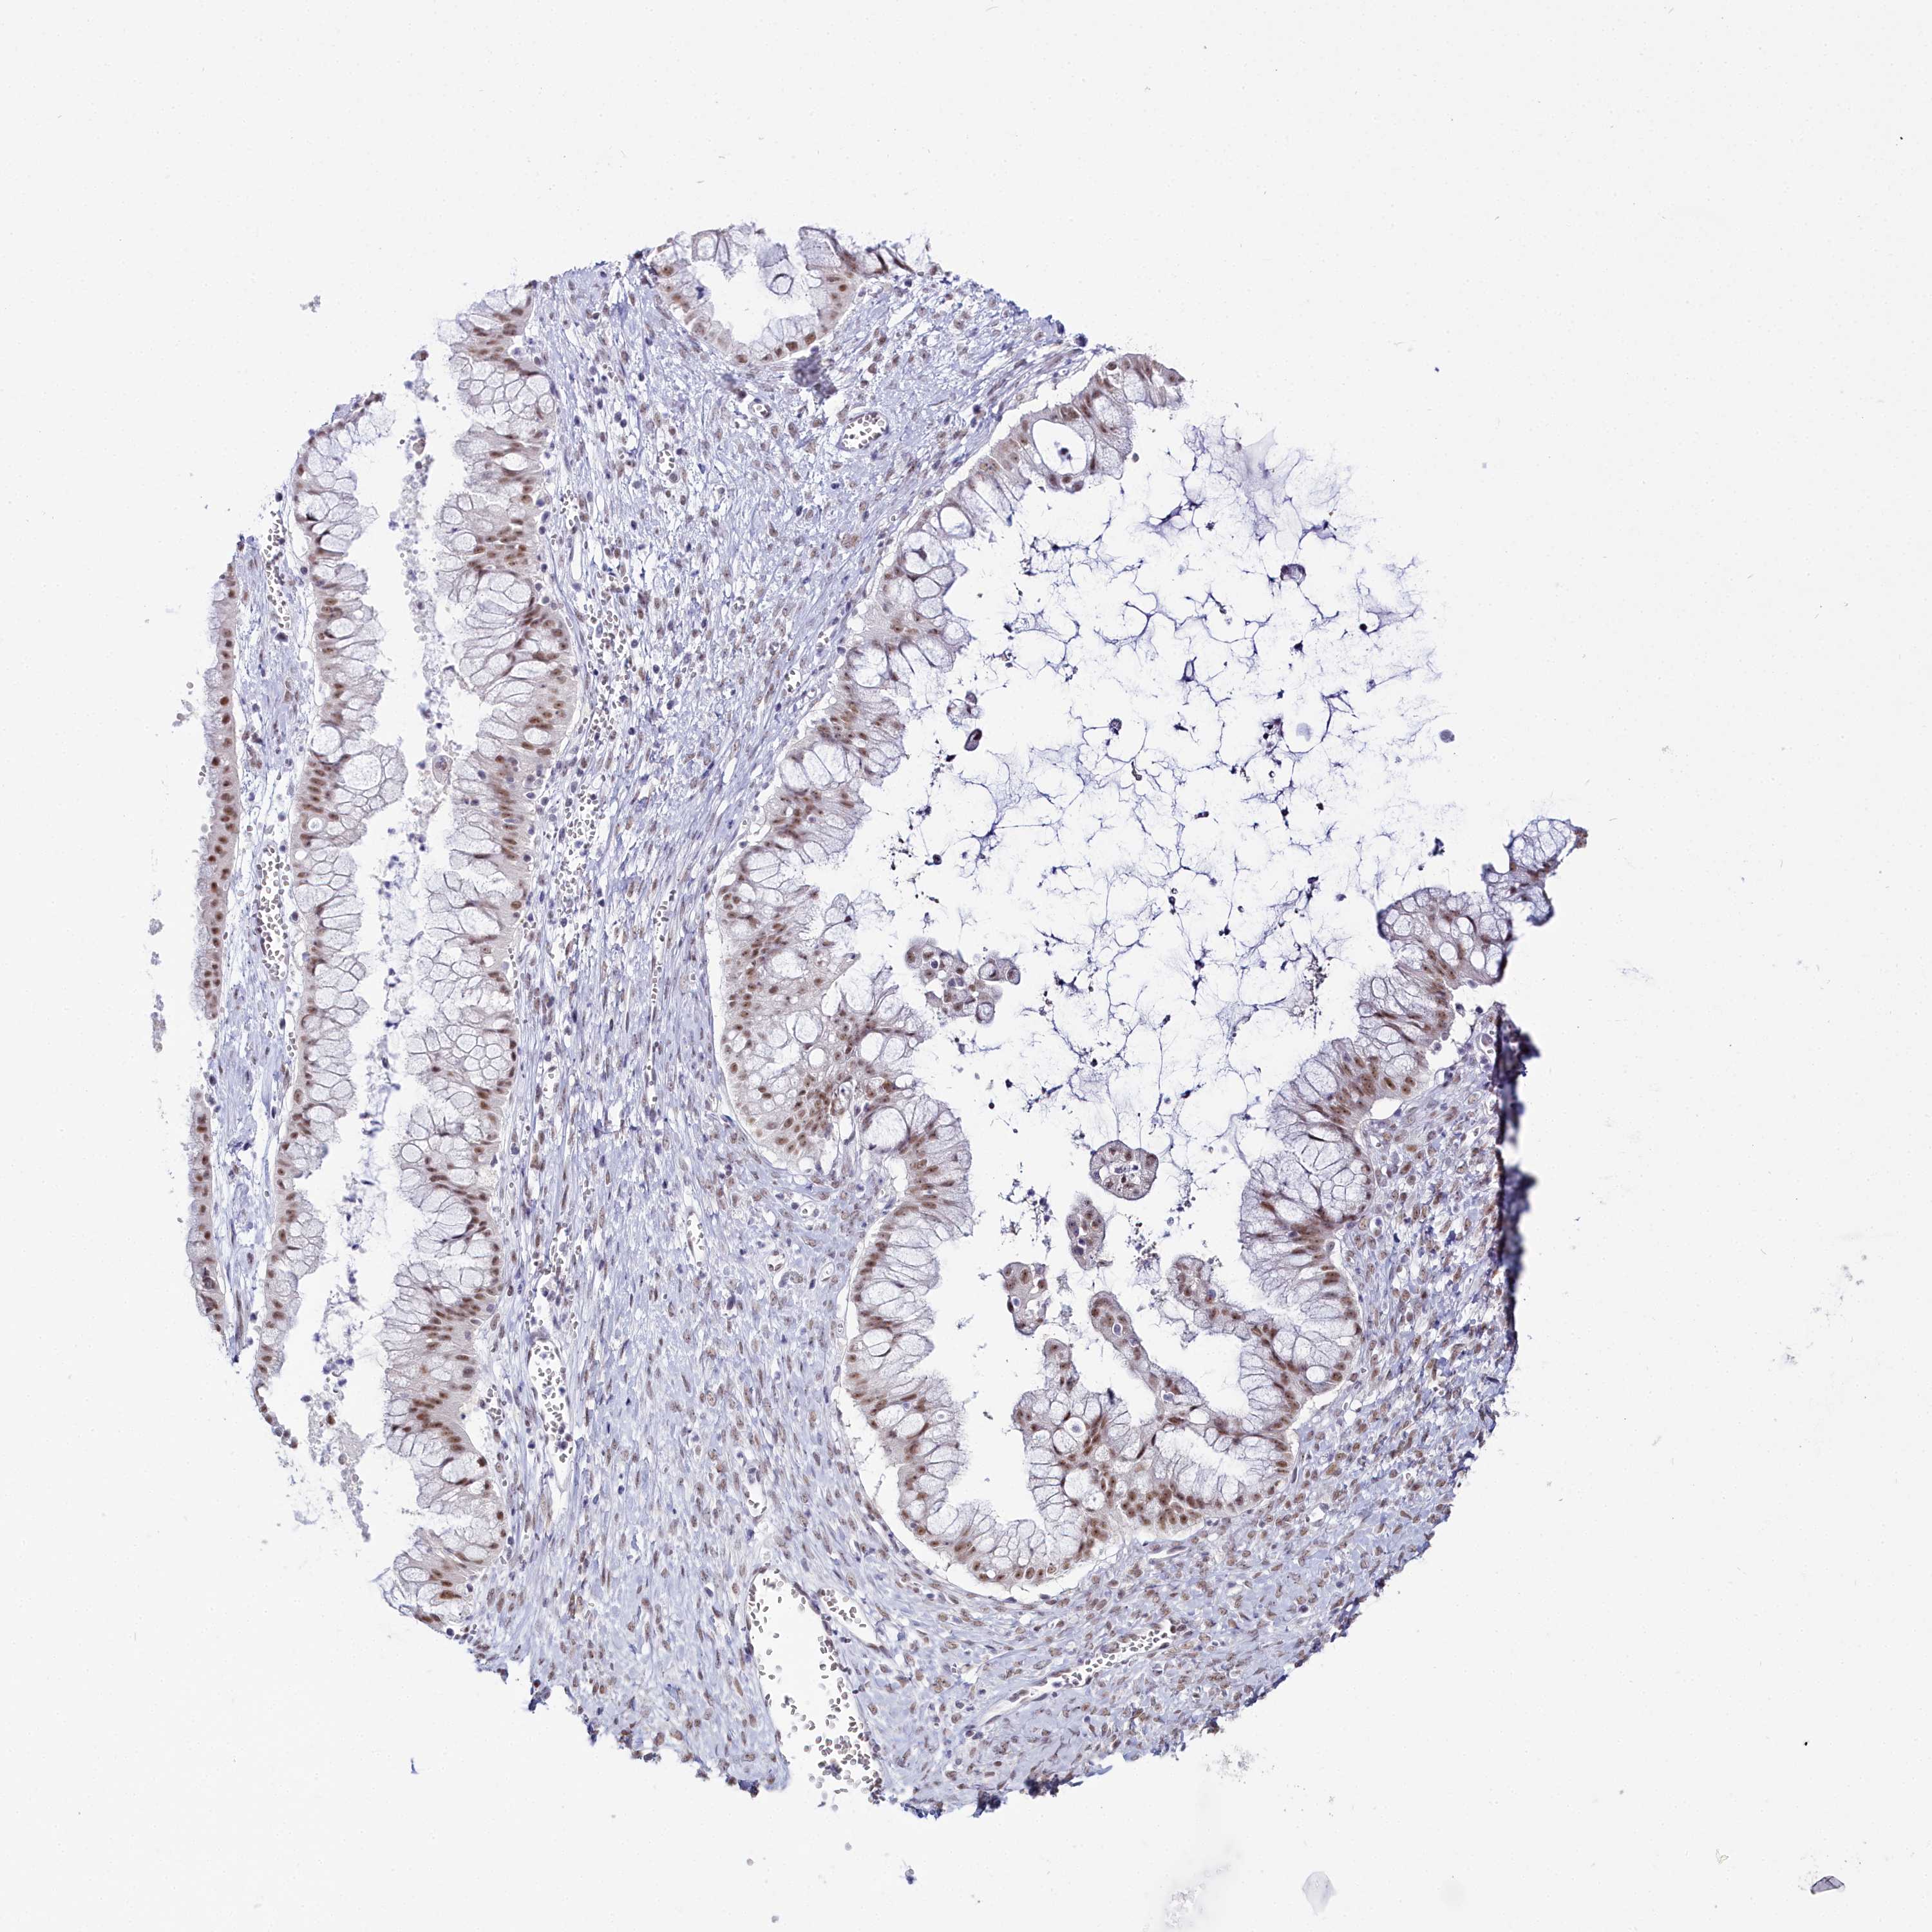

OVARIAN CANCER - Protein expressioni

A mouse-over function shows sample information and annotation data. Click on an image to view it in a full screen mode. Samples can be filtered based on level of antibody staining by selecting one or several of the following categories: high, medium, low and not detected. The assay and annotation is described here.

Note that samples used for immunohistochemistry by the Human Protein Atlas do not correspond to samples in the TCGA dataset.

Antibody stainingi

Antibody staining in the annotated cell types in the current human tissue is reported as not detected, low, medium, or high, based on conventional immunohistochemistry profiling in selected tissues. This score is based on the combination of the staining intensity and fraction of stained cells.

Each image is clickable and will lead to virtual microscopy that enables deeper exploration of all samples and also displays staining intensity scores, fraction scores and subcellular localization as well as patient and tissue information for each sample.

Antibody HPA043258

Antibody HPA043621

Staining

High

Medium

Low

Not detected

Intensity

Strong

Moderate

Weak

Negative

Quantity

>75%

75%-25%

<25%

None

Location

Nuclear

Cytoplasmic/membranous

Cytoplasmic/membranous,nuclear

Cystadenocarcinoma, serous, NOS

Carcinoma, NOS

Cystadenocarcinoma, mucinous, NOS

Carcinoma, endometroid